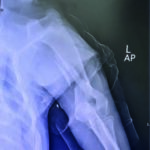

This case study involves a 5-monthsold, intact male Golden Retriever dog presented with tetraparesis, seizure and comatose by a car accident 5 days ago. Physical examination presented unconsciousness, tetraparesis, tachypnea, right temporomandibular joint (TMJ) luxated and crepitus of left humerus. Neurological examination was localized to cerebral cortex and brain stem lesions. The Modified Glasgow Coma Scale (MGCS) was 3. Laboratory tests revealed anemia of 23.1% (reference range, 35-45%), leukocytosis of 19.09 x 103/μL (reference range, 5-14.1 x 103/μL). Radiography was presented to skull fracture, lung hemorrhage (Figure 1) and left humerus fracture (Figure 2).